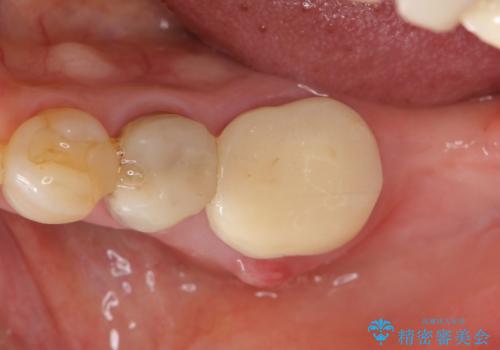

親知らずの移植 4年半経過症例 70代女性

- 親知らずの移植治療から4年半経過した患者様です。

移植した親知らずは全く問題ないそうで、「まるで自分の歯のようです。本当にすごい技術ですね。」とおっしゃって下さいました。

歯肉の腫脹や退縮、動揺も認められませんでした。

4年半前に行った自家歯牙移植に大変ご満足頂き、ご家族も紹介して下さいました。

自家歯牙移植は40歳以上の場合、若年者に比べ成功率が低くなるとの報告もありますが、状態によっては移植が可能な場合もあります。